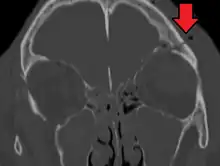

Basilar skull fracture

| A subtle temporal bone fracture as seen on CT in a person with a severe head injury | |

A basilar skull fracture is a break of a bone in the base of the skull.[1] Symptoms may include bruising behind the ears, bruising around the eyes, or blood behind the ear drum.[1] A cerebrospinal fluid (CSF) leak occurs in about 20% of cases and can result in fluid leaking from the nose or ear.[1] Meningitis is a complication in about 14% of cases.[2] Other complications include cranial nerve or blood vessel injury.[1]

They typically require a significant degree of trauma to occur.[1] The break is of at least one of the following bones: temporal bone, occipital bone, sphenoid bone, frontal bone, or ethmoid bone.[1] They are divided into anterior fossa, middle fossa, and posterior fossa fractures.[1] Facial fractures often also occur.[1] Diagnosis is typically by CT scan.[1]

Diagnosis

The evaluation for basilar skull fracture depends on a CT, as an x-ray is not useful.CT angiography and venography (CTA, CTV) may also be useful as an MRI can be used to ascertain nerve damage[4][8]